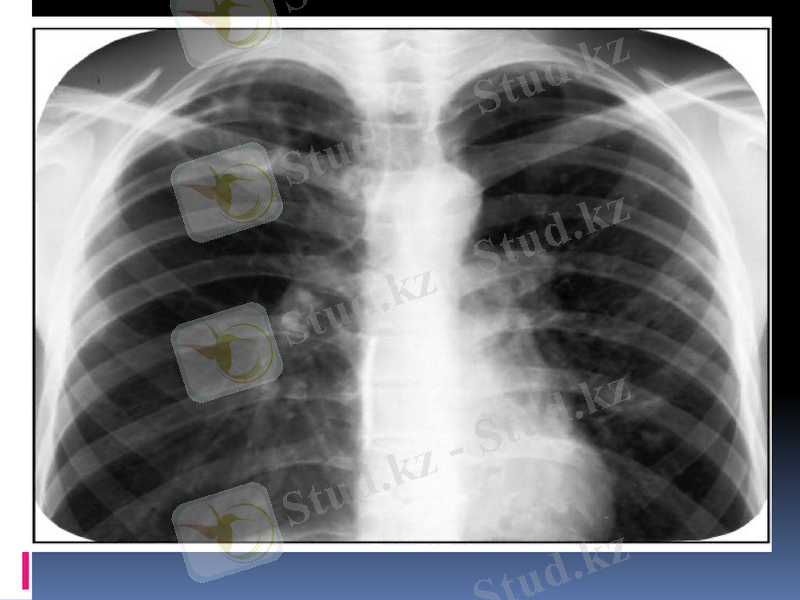

Кавернаның негізгі рентгенологиялық белгісі перпендикулярлы проекцияда сақталатын тұйық сақина тәрізді көлеңке болып табылады.

Сақина тәрізді көлеңкемен шектелген өкпе бөлігі кавернаның терезесі деп аталады. Айналасындағы өкпе тініне қарағанда, ол мөлдірлеу болады. Өкпенің элементтері негізделген құрылымдарында кавернаның терезесінде көлеңкелер көрінбейді